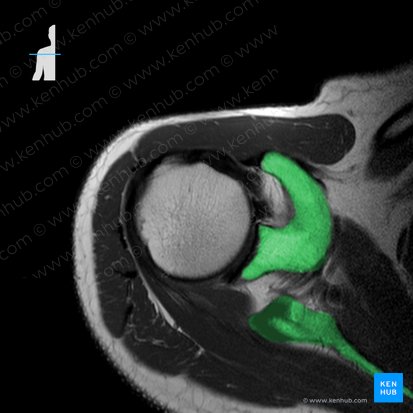

MRT ist ein bildgebendes Verfahren, das sich besonders gut zur Beurteilung von Gelenken eignet. Die MRT ermöglicht eine hohe Auflösung muskuloskelettaler Strukturen. Unten haben wir eine axiale MRT-Aufnahme der Schulter in PD-Gewichtung. Knochen erscheinen in der Aufnahme weiß, Muskeln dunkelgrau und Sehnen sowie Bänder schwarz.

Der äußere weiße Rand auf dem Bild ist die Haut und die Subkutis. Der weiße Kreis im Zentrum der Aufnahme ist der Humerus. Außerdem kann man gut den hellen Processus coracoideus und die Scapula erkennen. Das restliche Weichteilgewebe ist grau bis schwarz. In einer MRT-Aufnahme der Schulter sollte man die Weichteile in zwei funktionelle Gruppen unterteilen können: zum einen die statischen Stabilisatoren (Labrum glenoideum, Gelenkkapsel, Ligamentum glenohumerale und Ligamentum coracohumerale) und zum anderen die dynamischen Stabilisatoren des Schultergelenks (Rotatorenmanschette und die umgebenden Muskeln).

Zu den statischen Stabilisatoren des Schultergelenks zählen die Gelenkkapsel, das Labrum glenoideum und einige Bänder. Die Gelenkkapsel umgibt die Cavitas glenoidea, die sich in der Aufnahme als schwarze Struktur um den Humerus herum darstellt. Der fibrocartilaginäre Rand der Cavitas glenoidea ist das Labrum glenoideum, in der MRT ein kleine schwarze, dreieckige Struktur am Rand der scapulären Gelenkfläche.

Die Bänder der Schulter stabilisieren das Gelenk. Sie verhindern eine Dislokation des Humeruskopfes. Zu ihnen zählen das Ligamentum glenohumerale, das Ligamentum coracohumerale und das Ligamentum transversum humeri. Die ersten beiden entspringen am Labrum glenoideum und setzen am Humerus an, während das dritte den Sulcus intertubercularis bedeckt. Die Bandstrukturen des Schultergelenks erscheinen in der MRT als schwarze Streifen, deren Fasern in der Transversalebene ausgerichtet sind.

Zu den dynamischen Stabilisatoren gehören die Rotatorenmanschette, der Musculus biceps brachii und der Musculus triceps brachii. Diese Muskeln verstärken die Gelenkkapsel vor allem in Bewegung. Die Muskelbäuche und Sehnen der Rotatorenmanschette können in der Regel erst in nächster Nähe zur Gelenkfläche in der MRT gesehen werden. Die Bizepssehne ist normalerweise auf 12 Uhr vorzufinden. Wenn du sie an einer anderen Stelle entdecken solltest, dann stimmt etwas nicht. Die Sehnen dieser Muskeln sind sehr anfällig für Verletzungen (z.B. Sehnenruptur). Bei derartigen Verletzungen der Sehnen würde man die Läsion als hyperintenses (weiße) Signal in der MRT sehen können.